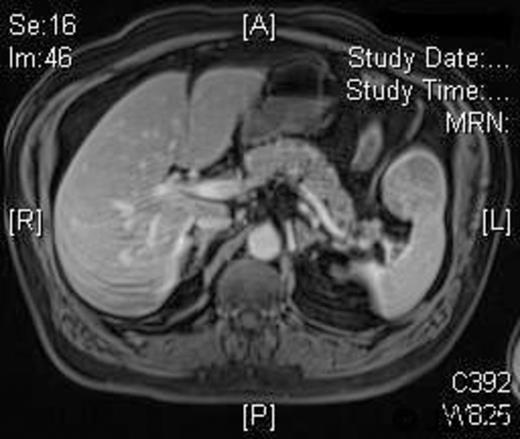

A 58-year-old Caucasian man presented with chest pain, on a background of type-II diabetes mellitus, hypertension and hypercholesterolaemia. A Cardiologist excluded ischaemic heart disease. Full blood count was normal, and an ultrasound scan of the abdomen revealed a 5.5-cm splenic lesion. Computed tomography (CT) revealed a 55mm X 36mm hypodense lesion in the upper pole of the spleen, while magnetic resonance imaging (MRI) demonstrated a well-circumscribed exophytic round mass arising from the anterior aspect of the spleen with features compatible with a benign solid tumour of uncertain malignant potential and multiple liver haemangiomas [Figures 1 and 2]. We proceeded to LPS after the patient had received preoperative vaccinations lest total splenectomy might be necessary.

T2W weighted image demonstrating a well circumscribed, round mass arising exophytically from the anterior aspect of the spleen with an intermediate T2W signal intensity.